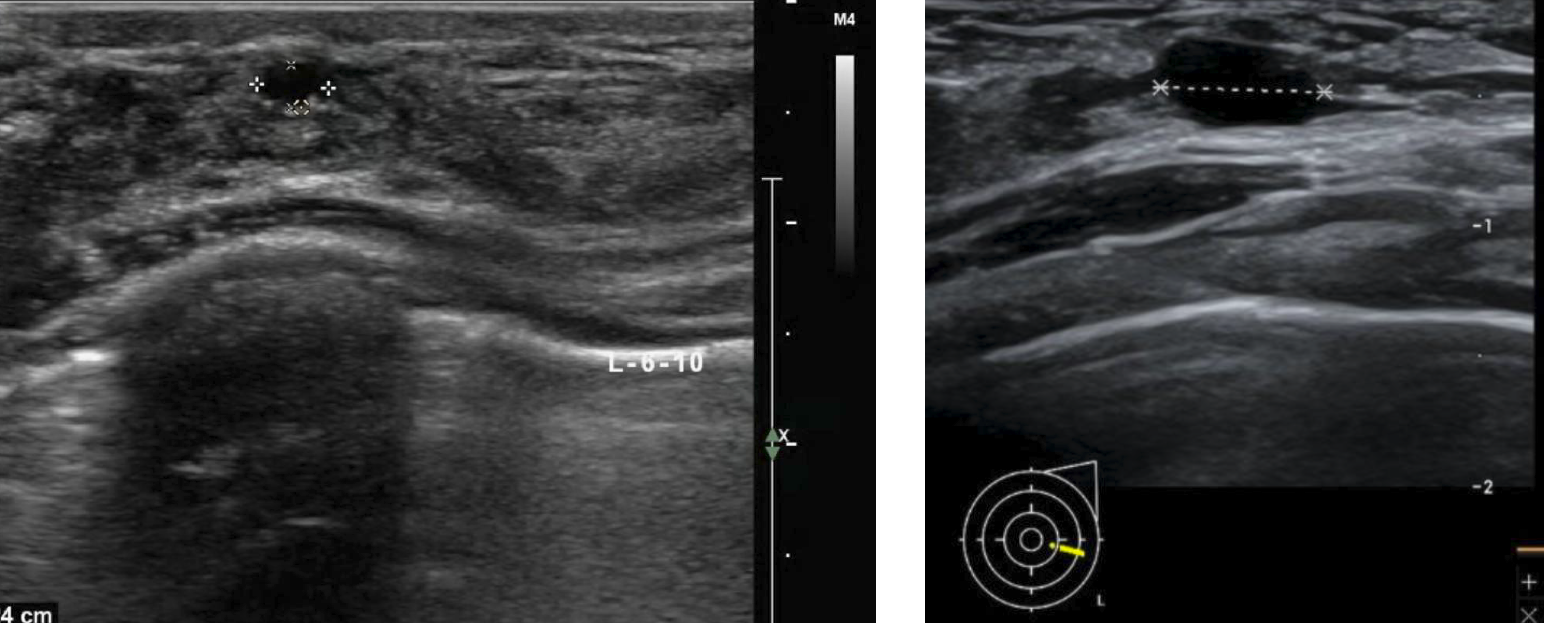

它太依赖侦探本人的经验。 手持B超有个“硬伤”,叫“操作者依赖性”。同一个花园,经验丰富的侦探可能每个角落都翻个底朝天;经验不足的,可能一扫而过,漏掉某个犄角旮旯。有专家指出,医生的经验和准确解读是早期诊断的关键[3]。

这名患者年年体检,左图为1年前结节情况,超声分级BIRADS3类,右图为今年彩超,结节增大明显,仍旧判定为BIRADS3类,建议患者手术,手术后证实为乳腺原位癌。